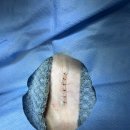

• 선부중앙동물의료센터 | 강아지 요로 결석 재발 재수술 후기

​ ​ ​ 강아지 결석 재발 재수술 후기 강아지 요로결석, 방광결석 재발로 재수술하게 된 후기 남겨봅니다. 반려견 결석은 재발률이 높은 편이라고 해서 꾸준히 관리...이번 수술은 선부중앙동물의료센터에서 진행했어요. ​ ​ ​ ​ 📍선부중앙동물의료센터 정보 주소 : 경기 안산시 단원구 선부광장1로 69 단지내상가동 2층...

참지않는 치와와(2026-03-28 13:21:00)